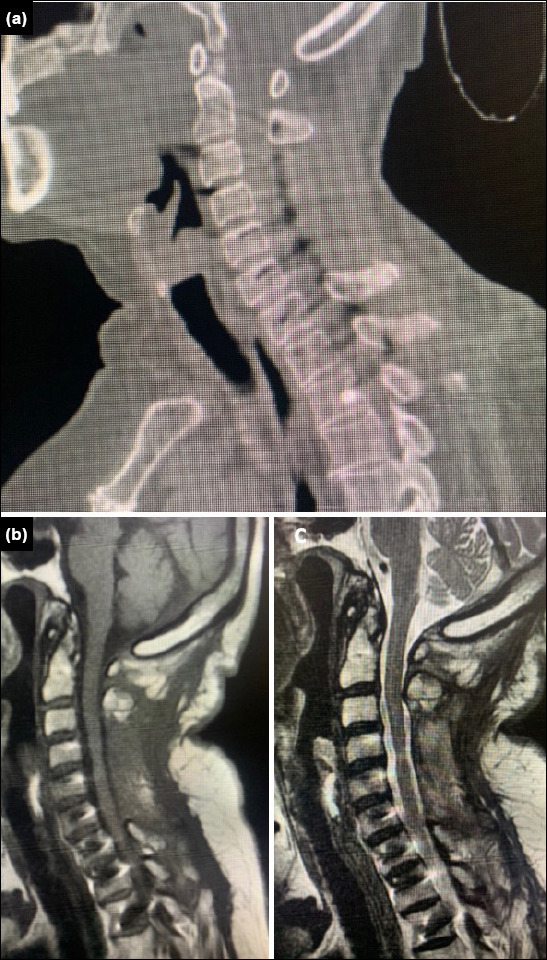

Methods: We retrospectively analyzed patients who underwent cervical subaxial pedicle screw placement between 2017 and 2024. A freehand surgical technique was employed, using a mini-laminotomy approach to ensure safe screw placement. During the procedure, the medial, superior, and inferior borders of the pedicle were palpated.

Results: A total of 70 cases were analyzed retrospectively. Fifty patients were male, and 20 were female. The patients ranged in age from 20 to 89 years (median age: 64 years). Fifty-seven patients (81.5%) had cervical stenosis as the surgical indication. Of the remaining cases, 11 patients had fractures and two had tumors. Among the 468 pedicle screws placed, 434 were graded as 0-1. The correct placement rate was 92.7%. Thirty-four screws were malpositioned (grade 2-3), representing a rate of 7.3%.